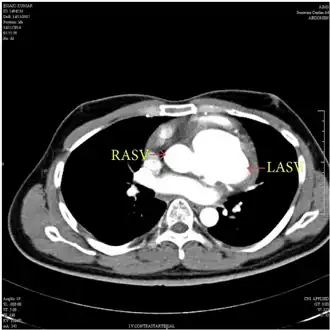

MDCT aortogram suggested left aneurysm of sinus of Valsalva and right aneurysm of sinus of Valsalva with extension into the interventricular septum. -

The first step in diagnosis is typically transthoracic echocardiography. However, if surgery is planned or if the standard echocardiogram lacks sufficient detail, then one or more additional studies are recommended. These studies include transesophageal echocardiography, 3D echocardiography, CT Angiography and aortic angiography.[4] Cardiac MRI may be another option.[2]